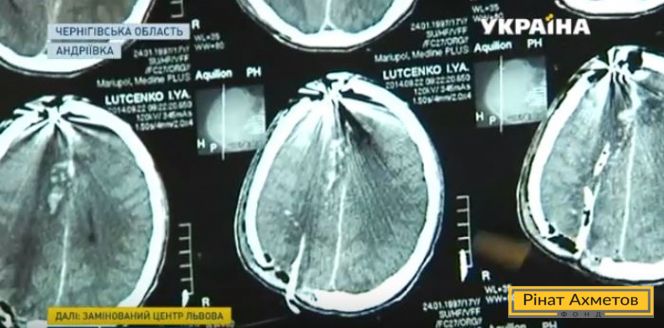

Снайпер прострелив голову студентові з Маріуполя, а він вижив. Лікарі називають це дивом. Іллю Луценка поранили восени 2014-го. Хлопець переніс кілька операцій і зараз проходить реабілітацію. Докладніше в сюжеті каналу «Україна».